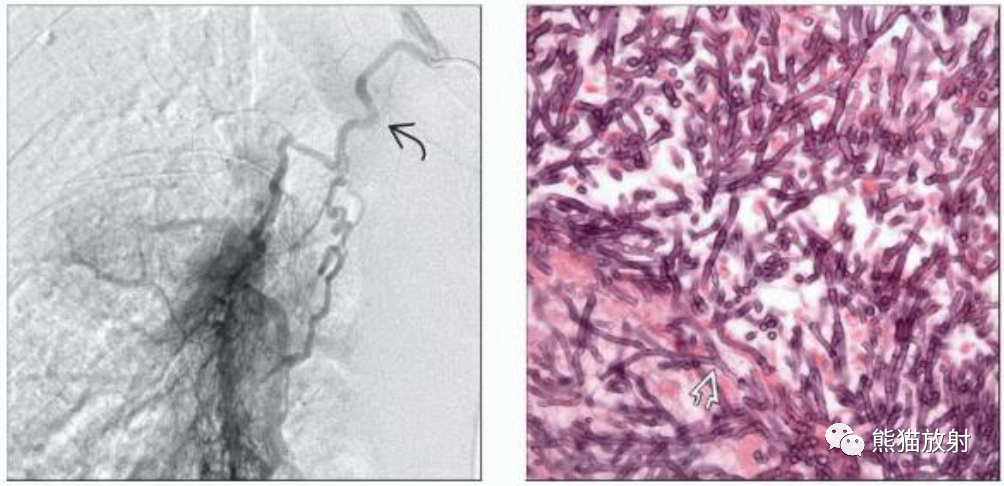

(左) 同一患者,支气管动脉栓塞过程中获得的DSA图像显示支气管动脉明显增粗,空洞性病变区域出现对比剂晕样显影。栓塞只是暂时成功,最终需要切除。

(右) 镜下可见真菌菌丝分支为45 ° 角,为典型的曲霉菌种。